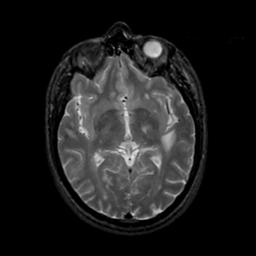

MR Study #22, December 1, 1991 -- Slice #24